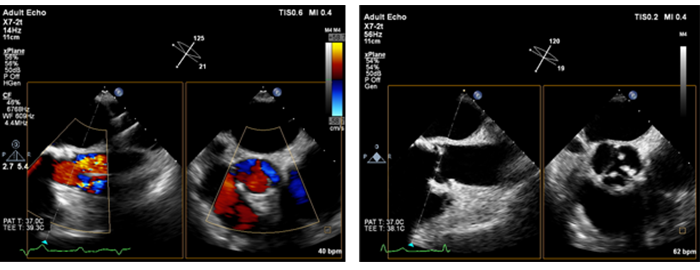

Live xPlaneイメージングは、フル分解能の断面を2断面同時に描出し、通常の2Dイメージングと同じ時間で2倍の臨床情報を取り込むことができます。

心臓検査でLive xPlaneイメージングを使用すると、同一心拍における2断面を同時収集し、重要な情報を迅速かつ確実に取り込むことができます。